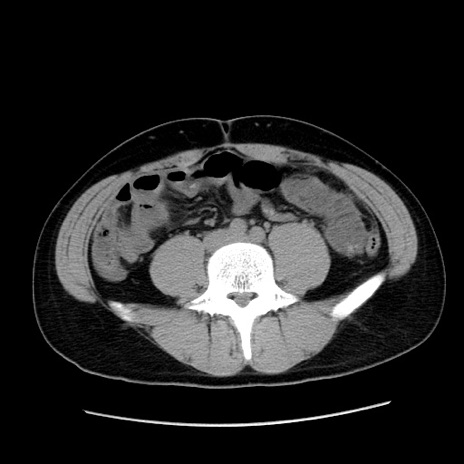

症例36(横断像)

【症例】20歳代 男性

【主訴】心窩部痛

【現病歴】今朝より上腹部痛あり。一旦軽快していたが再度出現したため救急要請。昨日夕に白身の魚を含む刺身を食べた。

【身体所見】BP 136/89mmHg、HR 74/min、BT 37.0℃、腹部:膨満、軟、心窩部に圧痛あり。反跳痛なし、筋性防御なし、腸雑音やや亢進あり。

【データ】WBC 17700、CRP 0.48